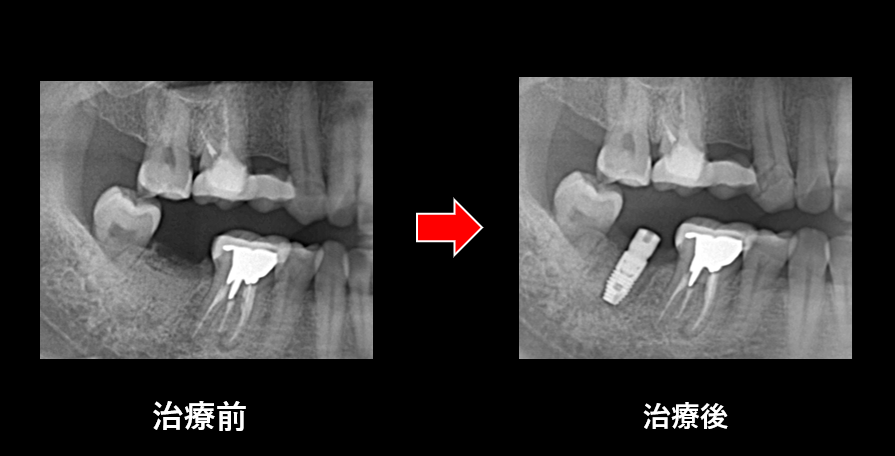

さて、先日も当院でインプラント手術行った症例をご紹介させていただきます。

📌 今回の症例について

今回の症例は、右下奥歯「7番」へのインプラント埋入でした

むし歯が重度のため保存不可能と判断し抜歯と同時に骨造成処置を行いました。

その後、骨造成された後、インプラント埋入手術を行いました。

術中・術後ともに特に問題なく、予定通りに埋入を終えることができました💡

ここから数か月かけて、インプラントと顎骨がしっかり結合する「オッセオインテグレーション🦴」を待ち、その後に最終補綴(かぶせ物治療)を行っていく予定です✨